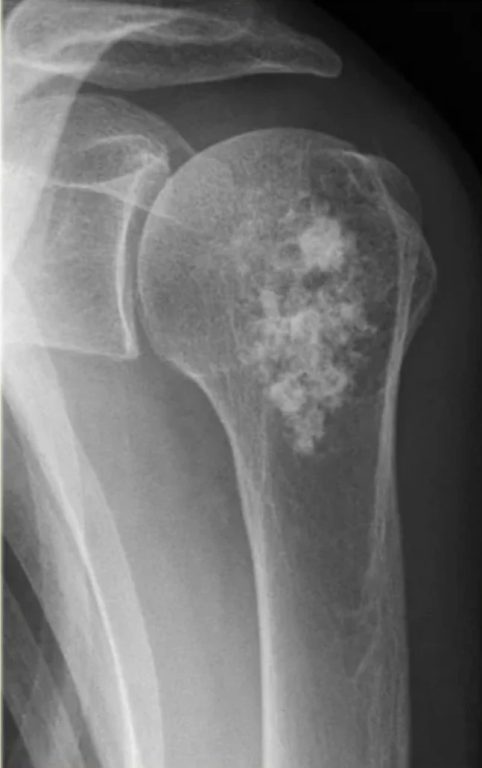

В основе инновационной разработки — радионуклид радий-223. Препарат «Ракурс, 223Ra» предназначен для лечения определённых видов онкологических заболеваний, преимущественно при метастазах в костях.

Радиоактивное излучение 223Ra целенаправленно воздействует на костные метастазы, уменьшая болевой синдром и улучшая качество жизни пациентов.